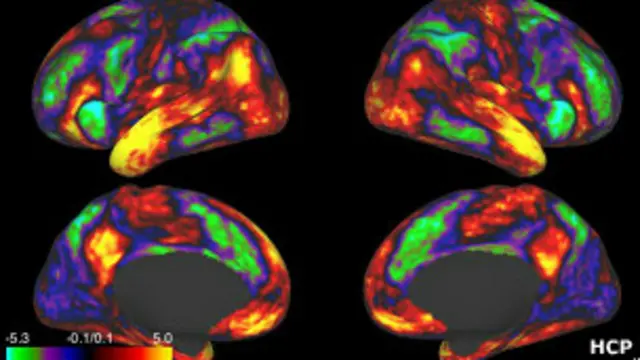

Исследование, проведенное методом магнитно-резонансной томографии, показало, что участки головного мозга, отвечающие за ощущение удовольствия, активизировались, когда люди слышали какую-либо песню в первый раз.

Анализируя ход сканирования, ученые обнаружили, что могут предсказать, какую песню выберет испытуемый: на мониторе томографа "центры удовольствия" заранее начинали ярко светиться.

Ученые обнаружили также, что "центры удовольствия" взаимодействуют с другой областью мозга - слуховой зоной мозговой коры. В ней хранится вся информация о ранее услышанных звуках и мелодиях.